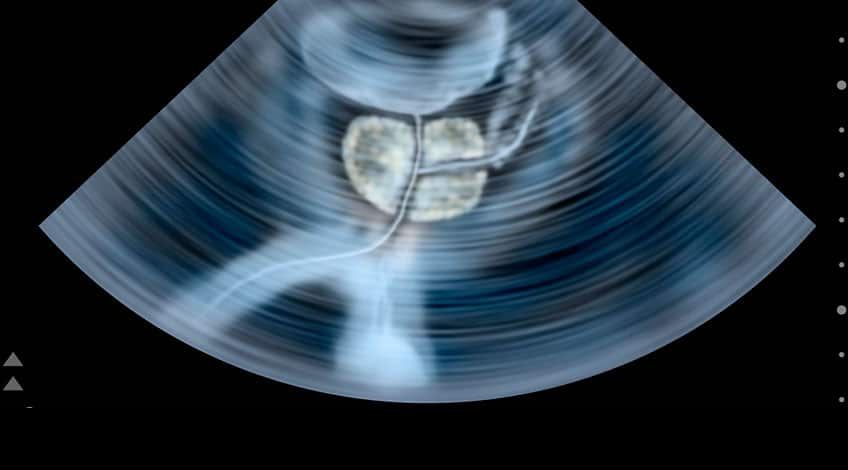

Ecotomografía Prostática

Con la ecografía prostática obtenemos imágenes de la glándula prostática y tejidos circundantes en el hombre. El examen por lo general requiere de la inserción de una sonda de ultrasonido en el recto del paciente.

Este examen se recomienda para detectar afecciones de la próstata, detectar si la próstata presenta un crecimiento anormal, ayudar a diagnosticar la causa de infertilidad en un hombre, estudiar nódulos encontrados en algún examen físico de rutina, resultados elevados en el análisis de sangre, dificultades para orinar, etc.